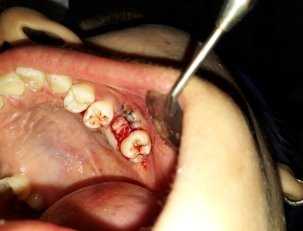

Клинический случай: Пац. А 18 лет. Амбулаторная история болезни № 13167. Обратилась день спустя после удаления 26 зуба. Анамнез: зуб был удален по поводу обострившегося хронического периодонтита. Жалобы: на хлюпанье — попадание воды в нос из полости рта, на боль пациент особо жалоб не предявила. Диагноз: перфорация верхнечелюстной пазухи в области 26 зуба. Методика оперативного вмешательства: под инфильтрационной анестезией (sol Articaini 1.5 мл — 2 %) промывали рану и лунку с антисептическим раствором содержащим метронидазол. (рис 1)

Техника пластики проводилась таким же путем как описано выше. (рис 2)